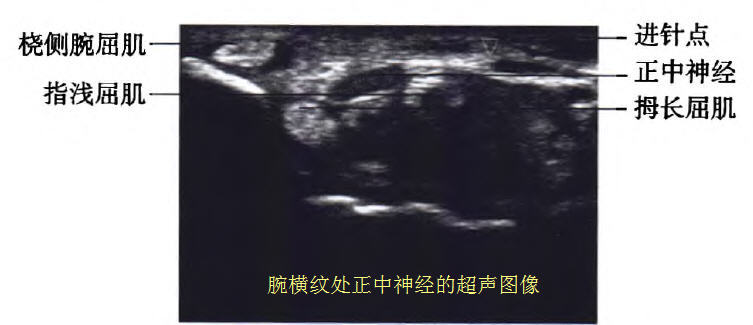

超声阻滞方法:所有患者取坐位,肘部以下置于检查床,手背下垫一块折叠的毛巾,采用超声下平面内尺侧入路。采用便携式超声仪高频直线探头,频率6~13 MHz,超声探头常规消毒,患者手腕部皮肤常规消毒后涂无菌耦合剂,探头长轴与手臂垂直,调节超声仪器的增益按钮,选择最清晰的画面,并且从画面中找到类椭圆形状的正中神经。

然后采用平面内技术,在超声的引导下从尺侧人路,针尖从指浅屈肌与指深屈肌之间穿行到达正中神经的神经鞘膜附近。